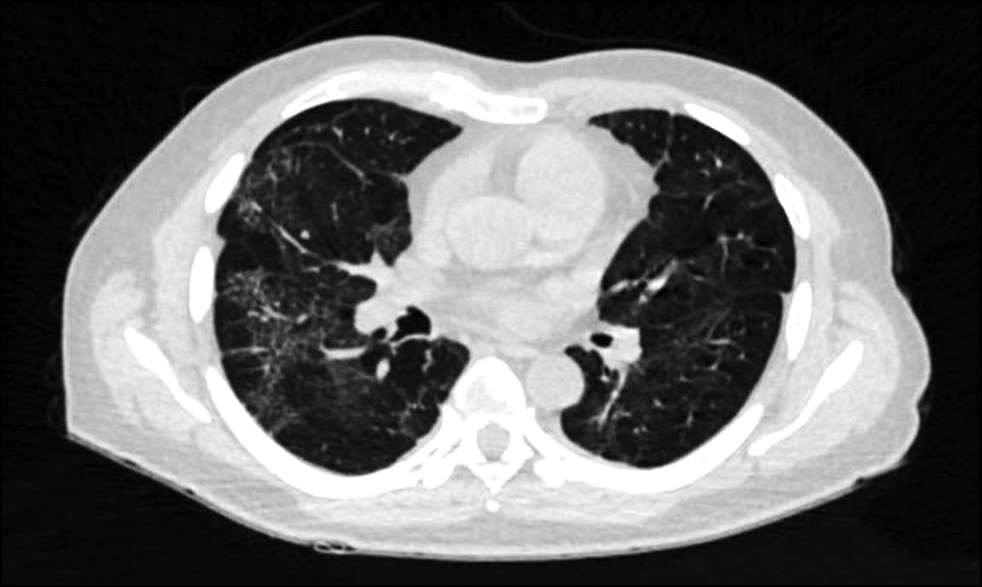

КТ органов грудной клетки выполнялась с целью исключения очагов диссеминации в легочной ткани (рис. 7).

Рис. 7. КТ органов грудной клетки, аксиальная плоскость. С обеих сторон отмечаются остаточные изменения двусторонней вирусной пневмонии — интерстициальные изменения и криволинейные уплотнения легочной ткани